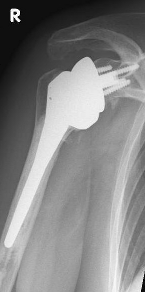

Abbildung9Abbildung10 Special prostheses such as an inverse shoulder prosthesis (syn.: "Delta prosthesis", "Grammont prosthesis") for the combination of severe omarthrosis with joint instability and rotator cuff defects

Right: radiograph of an inverse shoulder prosthesis for rotator cuff defect arthropathy.

left: Inverted shoulder prosthesis (Aequalis reversed type, Tornier company).